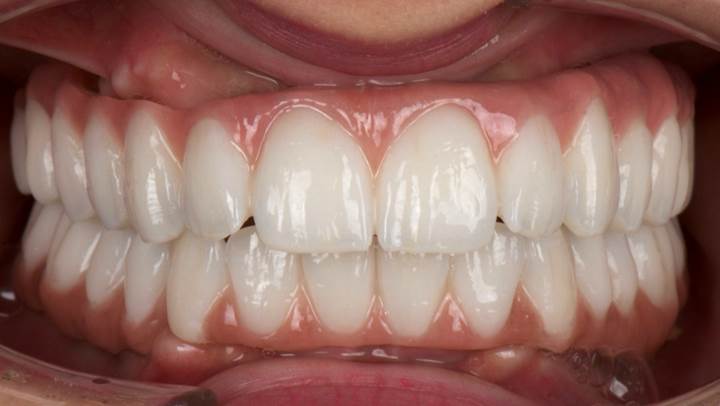

Clinical case: AFull transition from natural teeth to all-on-6 bridges

with AnyRidge implants

- Courtesy of Dr. Rabih Abi Nader, UAE -

“AnyRidge shows excellent esthetic results

with Zirconia prosthesis in full-mouth rehabilitation case . ”